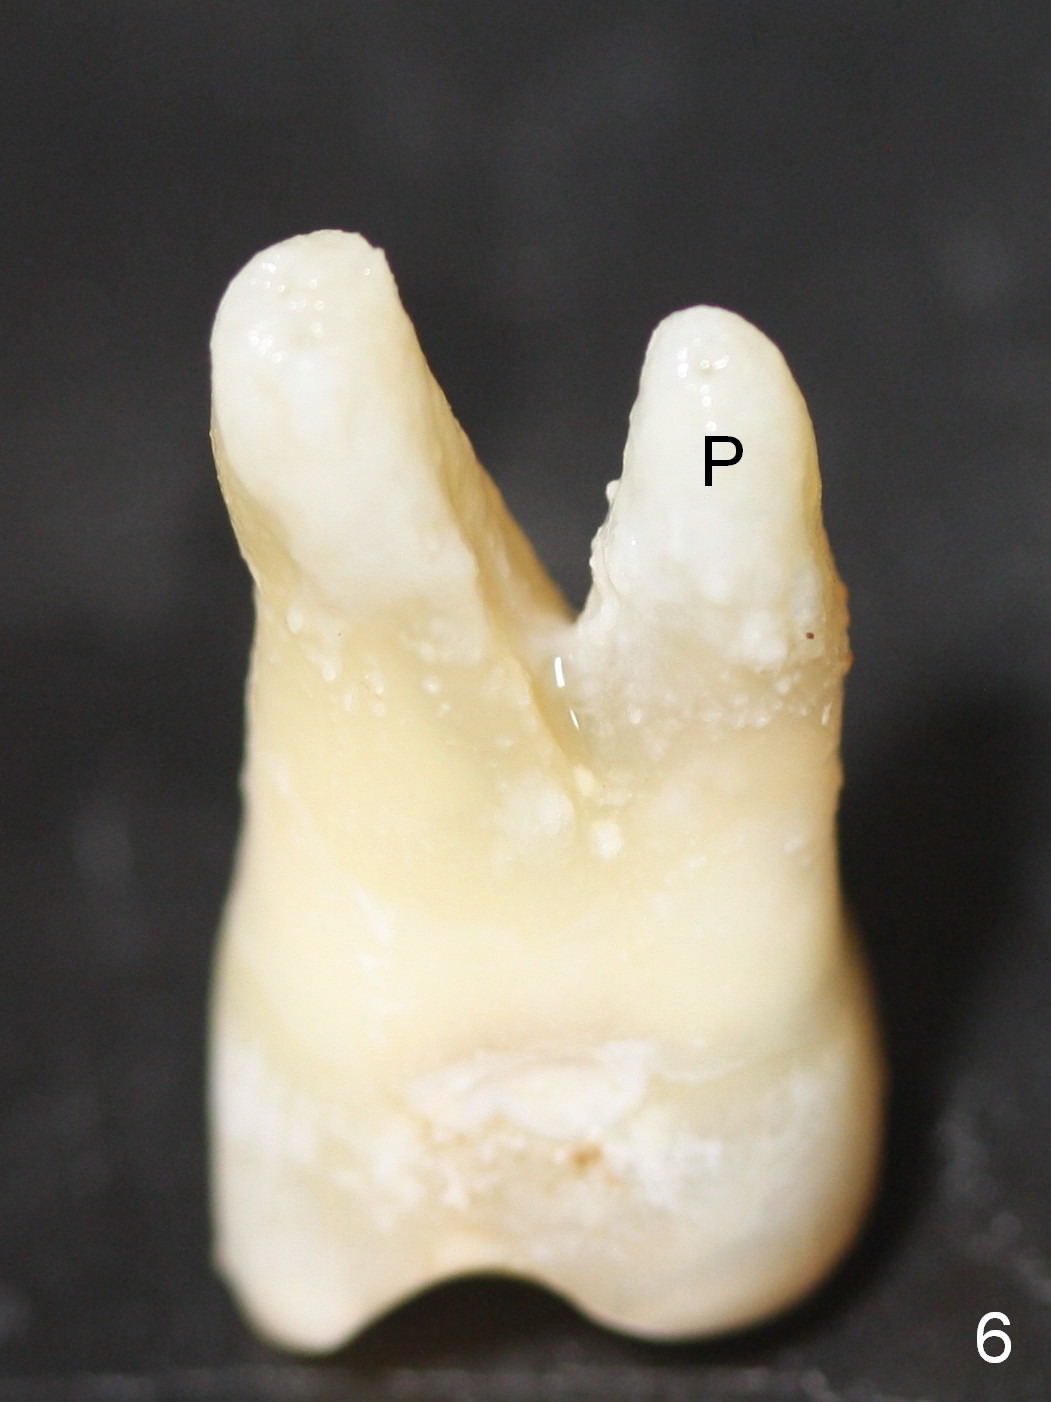

The furcation of the upper 2nd molars is variable. For example, the buccal roots of the 2nd molar may be fused (Fig.4-6). The septum may be destroyed due to infection such as in this case (Fig.4). An immediate implant could be placed in the septum or the buccal and palatal sockets, depending upon the integrity of the buccal and palatal plates.